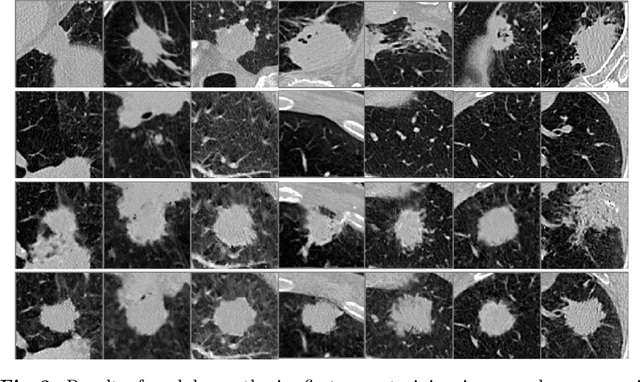

Abstract:Radiogenomic map linking image features and gene expression profiles is useful for noninvasively identifying molecular properties of a particular type of disease. Conventionally, such map is produced in three separate steps: 1) gene-clustering to "metagenes", 2) image feature extraction, and 3) statistical correlation between metagenes and image features. Each step is independently performed and relies on arbitrary measurements. In this work, we investigate the potential of an end-to-end method fusing gene data with image features to generate synthetic image and learn radiogenomic map simultaneously. To achieve this goal, we develop a generative adversarial network (GAN) conditioned on both background images and gene expression profiles, synthesizing the corresponding image. Image and gene features are fused at different scales to ensure the realism and quality of the synthesized image. We tested our method on non-small cell lung cancer (NSCLC) dataset. Results demonstrate that the proposed method produces realistic synthetic images, and provides a promising way to find gene-image relationship in a holistic end-to-end manner.